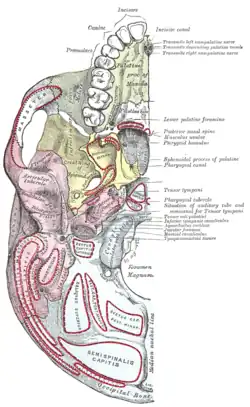

Base of the skull, inferior or outer surface. Showing various muscle attachments. | |

Base of the skull. Inferior surface, attachment of muscles marked in red.